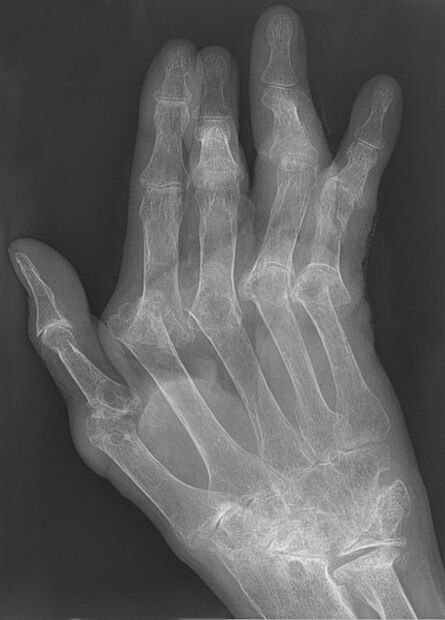

При ревматоидном артрите из-за аутоиммунной реакции воспаляются, а затем деформируются суставы. Пациенты достаточно быстро теряют подвижность и становятся инвалидами, поэтому важно начать лечение как можно быстрее, чтобы замедлить прогрессирование болезни. Лечат ревматоидный артрит препаратами, блокирующими воспаление, которые надо принимать постоянно и в больших дозах. Долговременная терапия такими препаратами приводит к множеству побочных эффектов: от тошноты и диареи до частых инфекций.